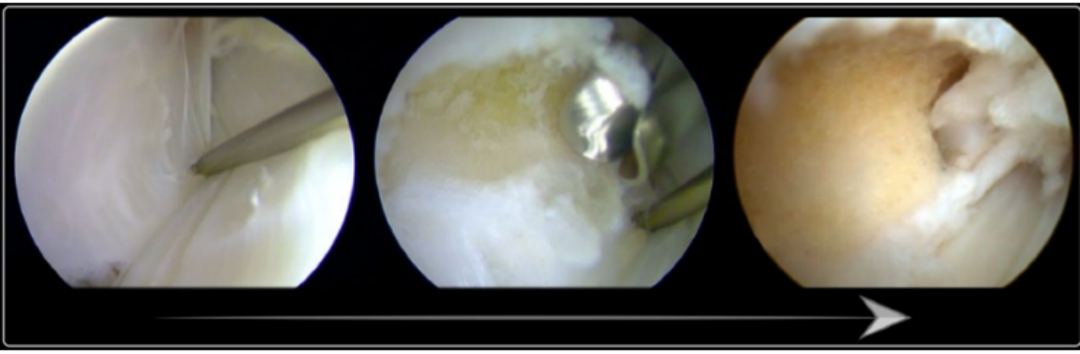

SPR撕脱关节镜手术锚钉修复

内镜下腓骨沟加深手术

大部分急性损伤可以使用直接缝合修复,对慢性损伤则需根据患者的具体病理改变选择,如单纯的支持带结构损伤,可以直接缝合修复。如果直接修复不够稳定,需用其他组织加强。如果腓骨外踝窝较浅时,就需要使用加深手术。